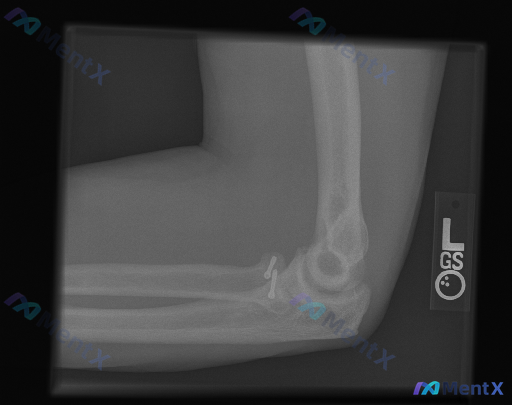

整理到一张左侧肘关节侧位X光片的分析资料,先不直接说结论,大家看第一遍的时候,最突出的「与正常不同」会先注意到什么? 先提几个观察点: - 骨骼完整性/有没有异常高密度影 - 关节对位关系 - 关节周围软组织 这份资料的核心其实不只是识别异常,而是对异常性质的定性——哪些是医源性的预期改变,哪些是需...